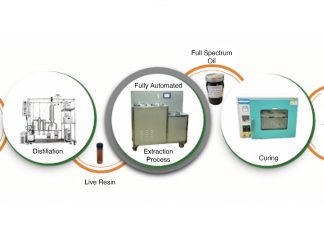

New bone cancer treatment could save children’s lives

Researchers at the University of East Anglia and The University of Sheffield have developed a new bone cancer treatment for children.

Currently, bone cancer treatment...

Researchers have developed a revolutionary new bone cancer treatment

Researchers from the University of East Anglia (UEA) have developed a new, non-invasive bone cancer treatment that is effective against all primary forms of...